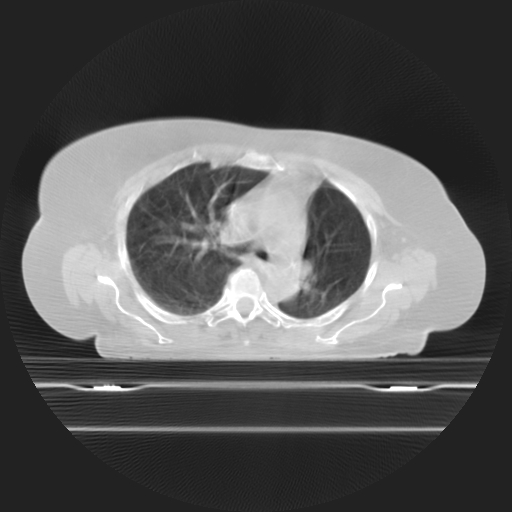

Planning CT Images